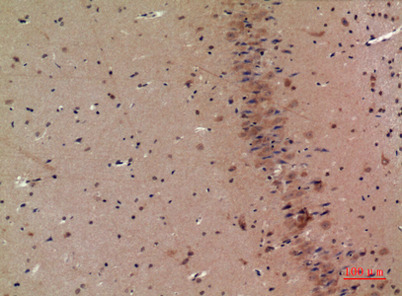

| Dilutions: | Western Blot: 1/500 - 1/2000. Immunohistochemistry: 1/100 - 1/300. Immunofluorescence: 1/200 - 1/1000. ELISA: 1/5000. Not yet tested in other applications. |